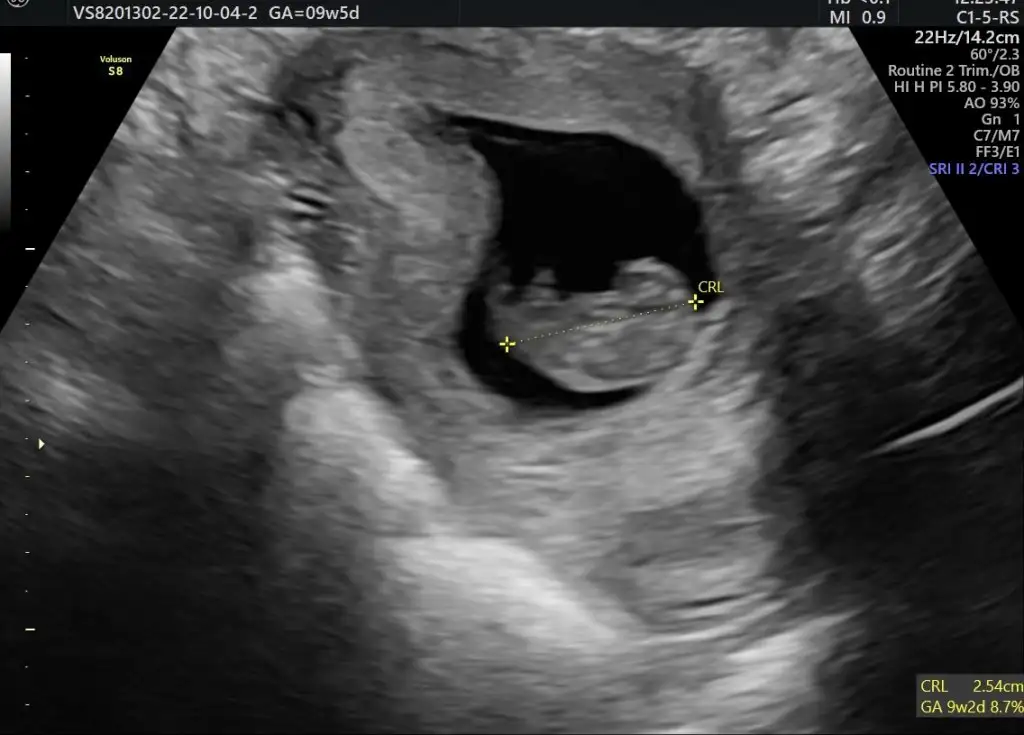

Dün bebişlerimi gördüm yine büyümüş keratalar 😄 (9+4 ölçüldüler)

Paylaşim ama henüz biseye benzemiyor bacaklari kolları henüz tomurcuk dedi 🥰

Eklentiler

• 04D15D30-EB44-4811-B1F3-120F1BEA2A68.webp

04D15D30-EB44-4811-B1F3-120F1BEA2A68.webp

29,9 KB · Görüntüleme: 50